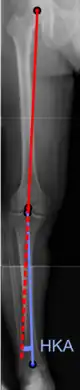

Radiography

On projectional radiography, the degree of varus or valgus deformity can be quantified by the hip-knee-ankle angle,[7] which is an angle between the femoral mechanical axis and the center of the ankle joint.[8] It is normally between 1.0° and 1.5° of varus in adults.[9] Normal ranges are different in children.[10]

Hip-knee-ankle angle

Hip-knee-ankle angle Hip-knee-ankle angle by age, with 95% prediction interval[10]

Hip-knee-ankle angle by age, with 95% prediction interval[10]